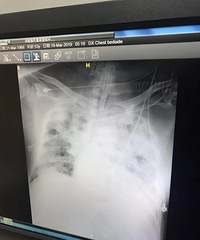

外婆脚痛住院,挂针挂出胃大量出血,生命垂危,全身血液大换血